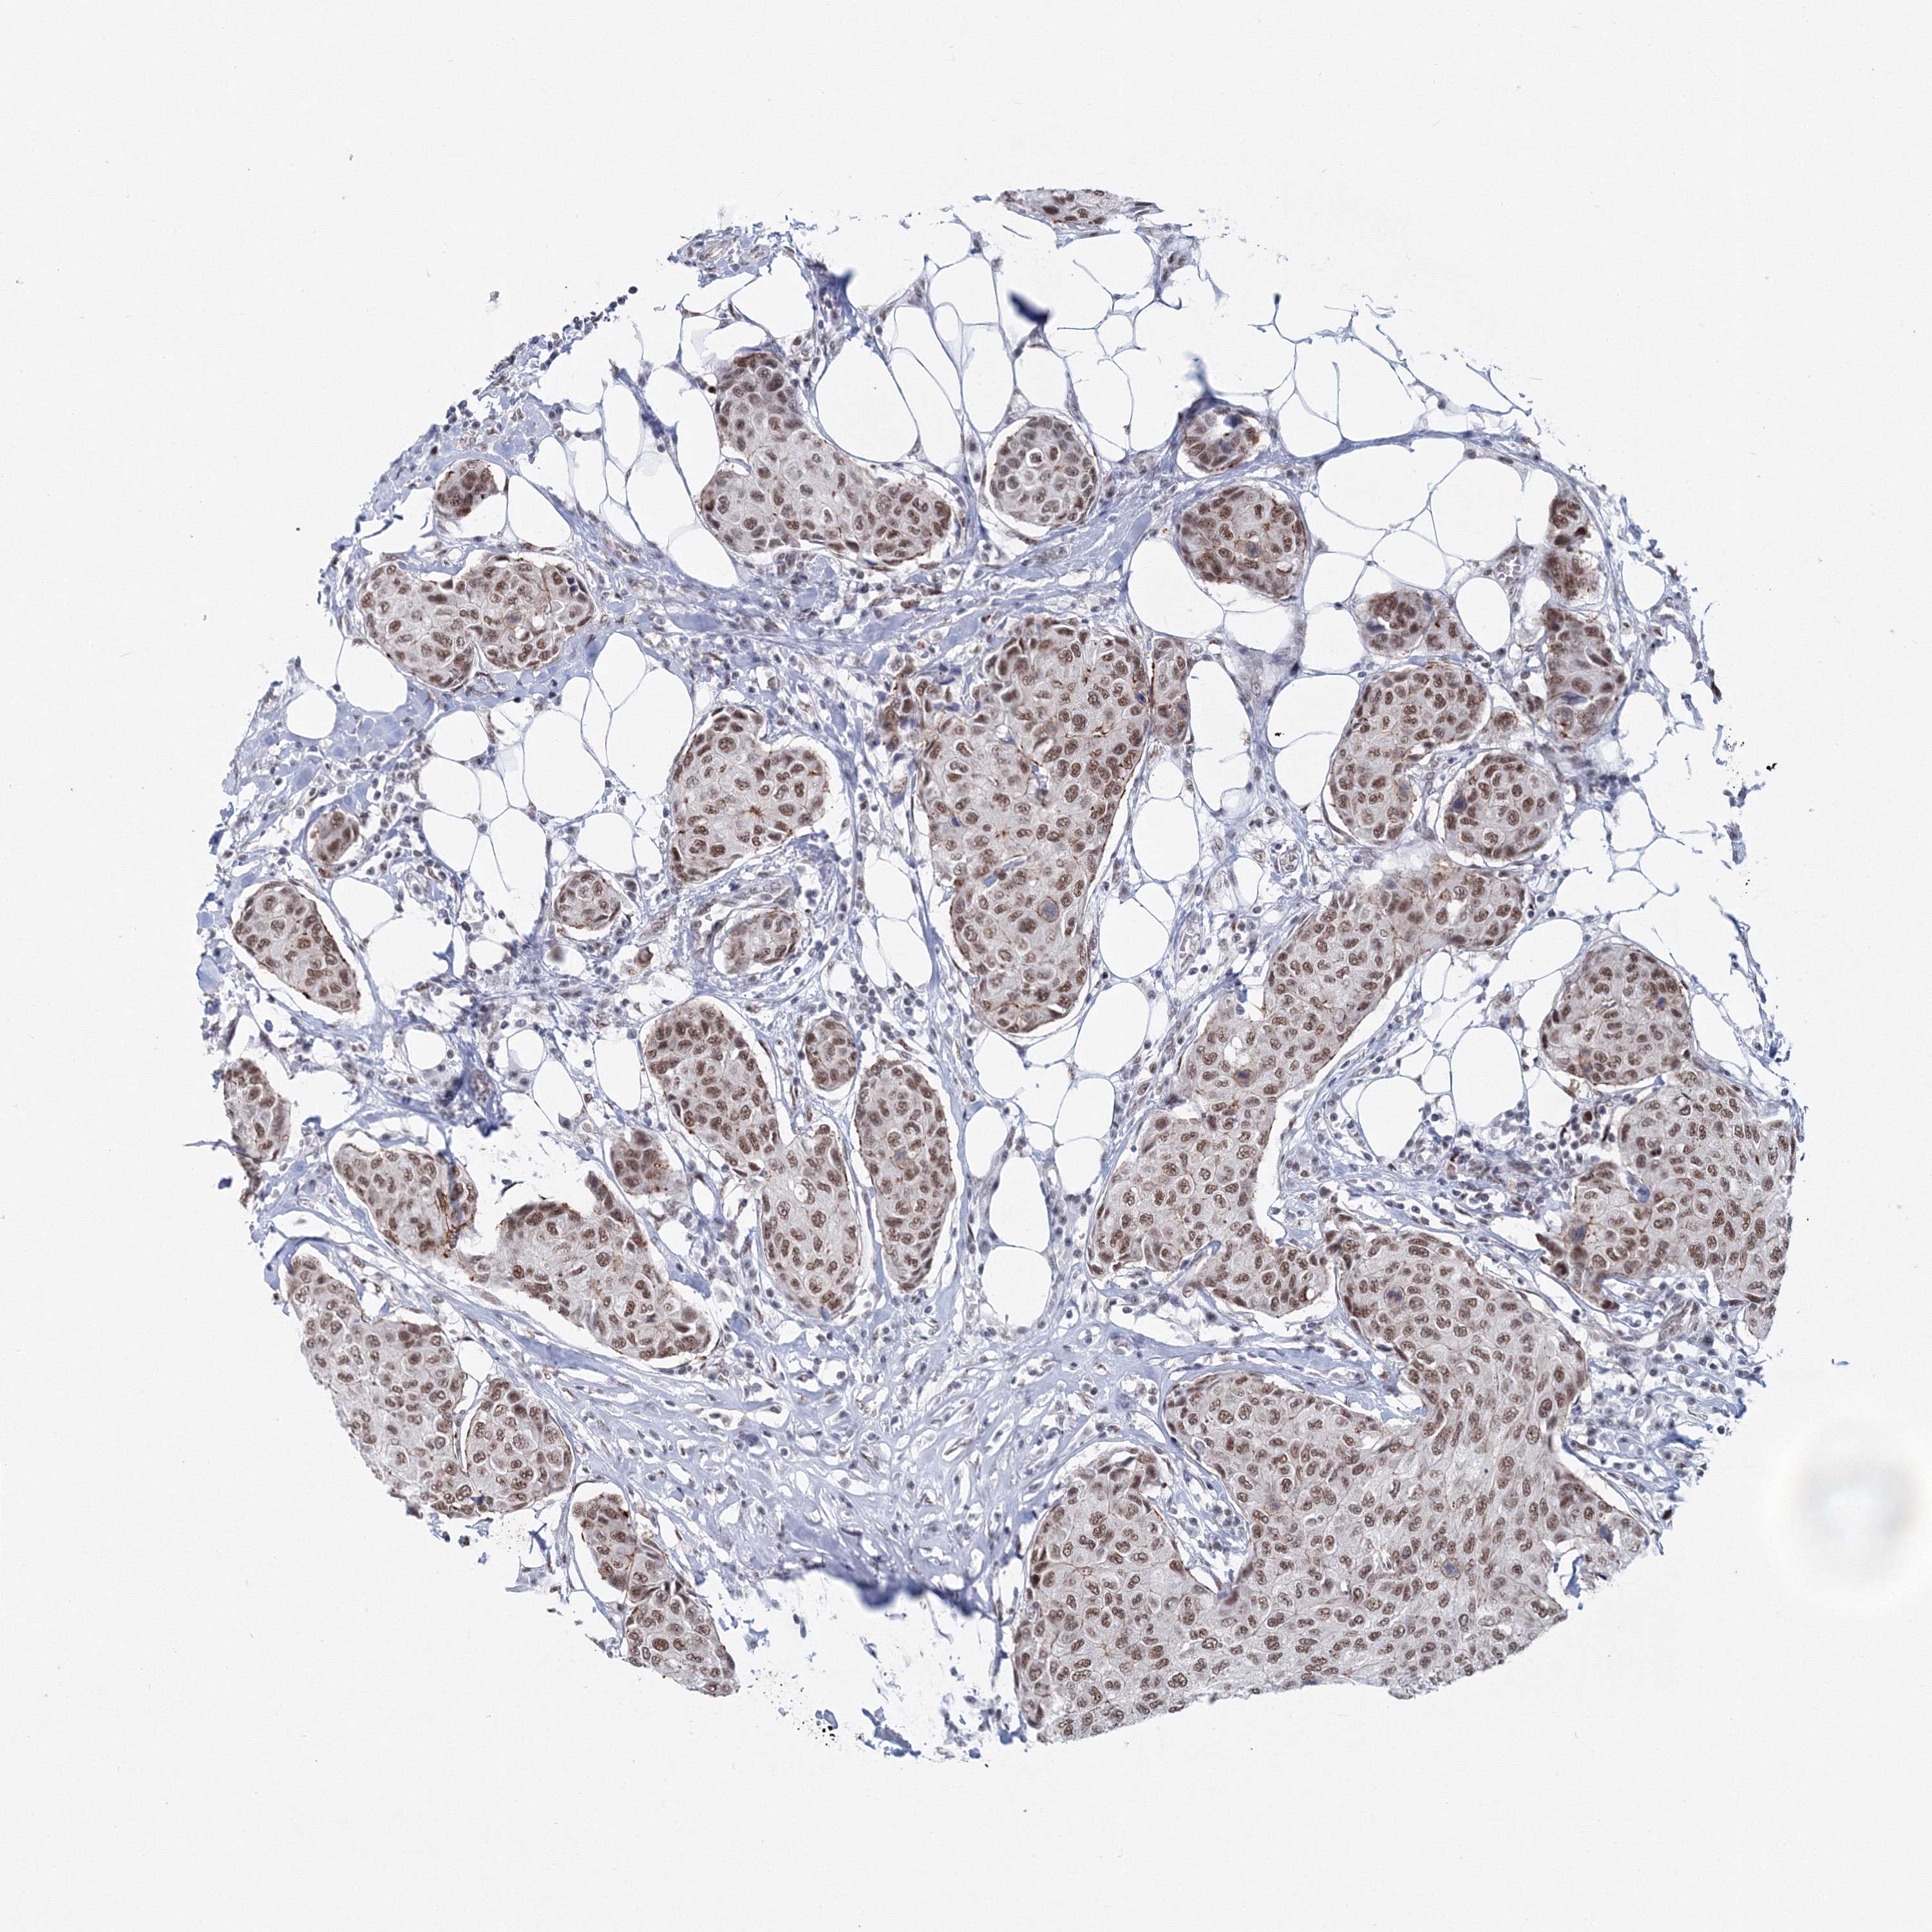

CANCER BREAST CANCER Show tissue menu

BRCA TCGA BRCA VALIDATION PROTEIN EXPRESSION

ANTIBODIES

AND

VALIDATION